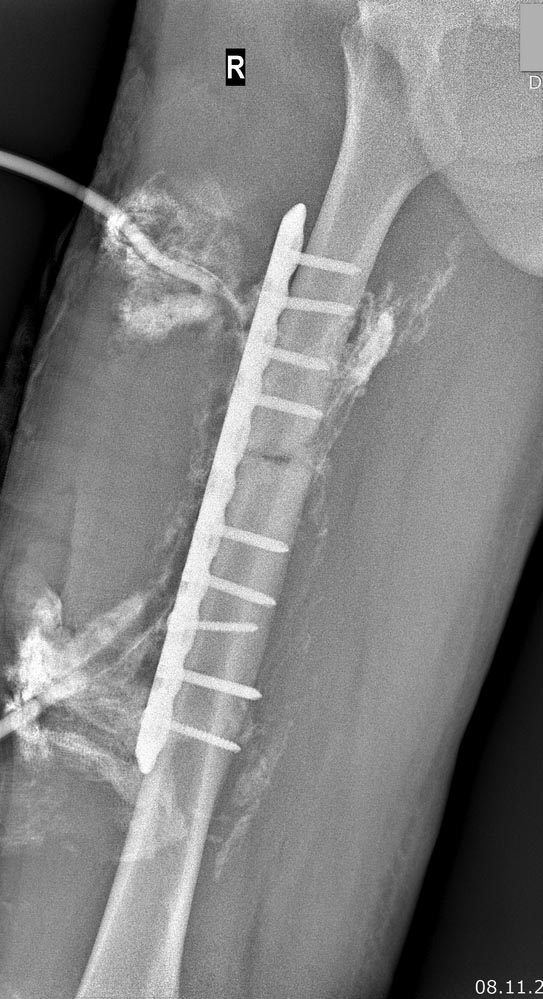

Коллеги, просьба Вашего мнения по тактике.

Пациент 45 лет, без значимых сопутствующих. В середине октября 2017–

ДТП, оперирован по месту ДТП. Первичных снимков не предоставил.  Через 2

недели - картина глубокой флегмоны правого бедра.

Фистулография после первичного дренирования флегмоны–  см вложение. При

ревизии выявлено, что не менее 3/4 окружности диафиза бедра

скелетированы по всему длиннику пластины, А на уровне проксимального

отломка на протяжении не менее 6-7 см–  циркулярное скелетирование.

Пластина удалена. АНЧКФ. При ревизии раны по медиальной поверхности

вертикализации. СОЭ 20-30, СРБ 15-20. Вложение: фистулография в начале,

Рг-контроль, внешний вид, выборка МСКТ от 20.02.18 в jpeg по ссылке: